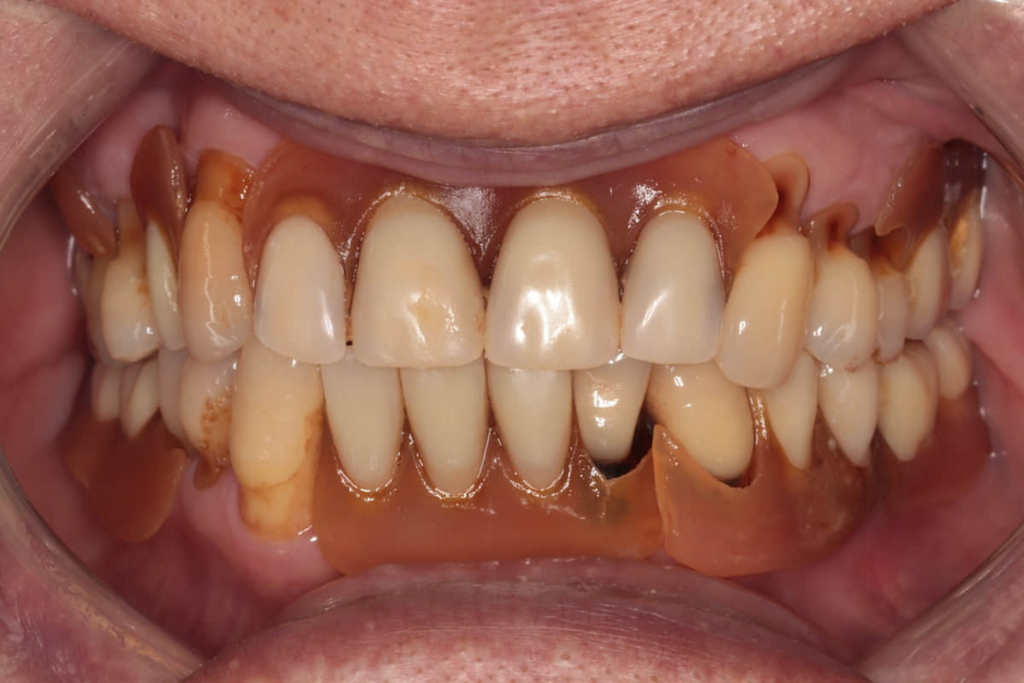

術後配戴正式假牙